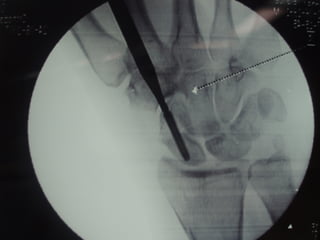

 With advent of percutaneous techniques of

cannulated screws under flouroscopic control trend

towards operative management

Management of waistfractures  Most stable fractures can be treated with below elbow thumb spica  Unstable fractures best treated with compression screw fixation – >1mm displacement – Fragment angulation – Abnormal carpal alignment  With advent of percutaneous techniques of cannulated screws under flouroscopic control trend towards operative management